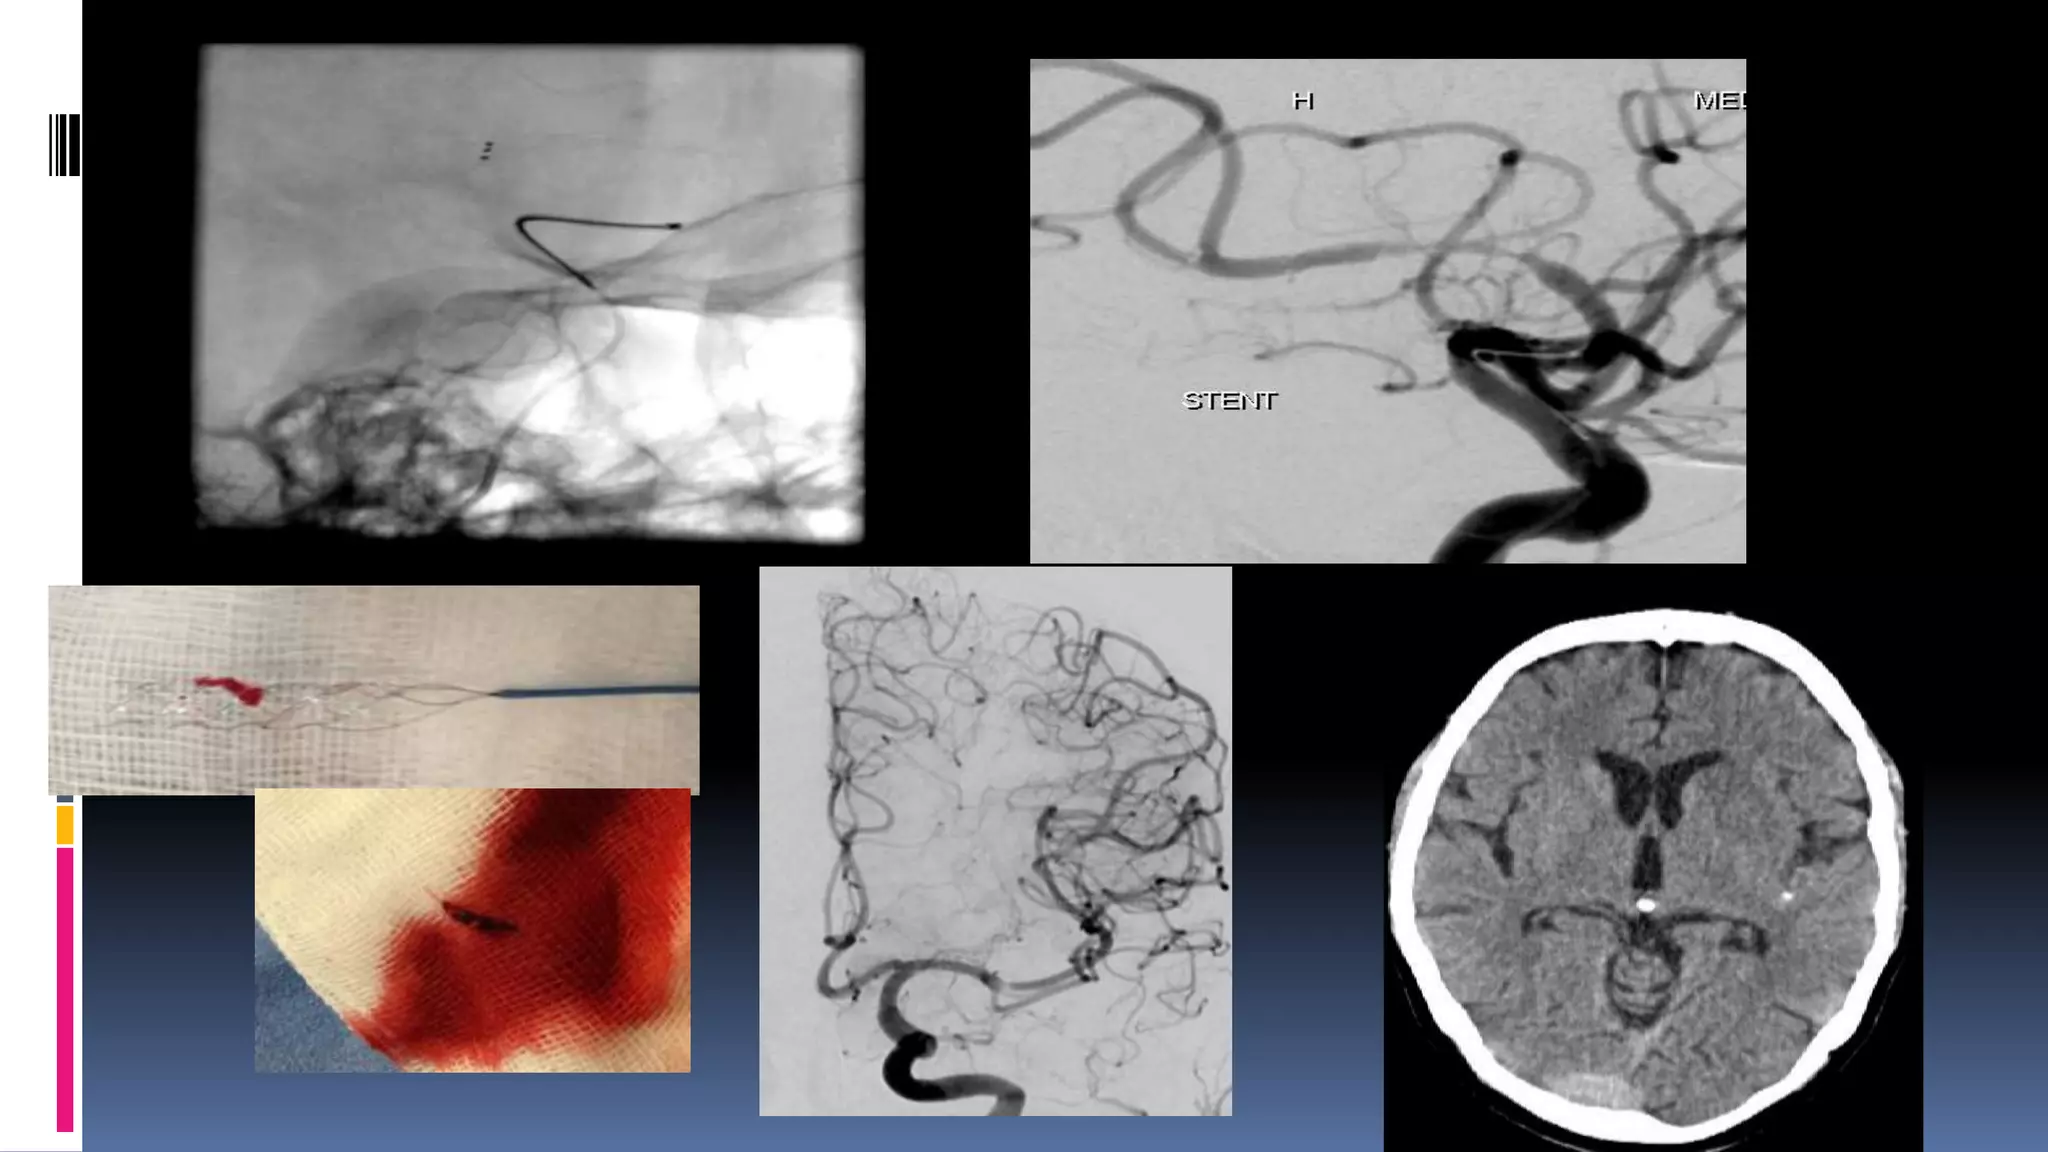

Left terminal ICA with Bovine arch Type 2 and type 3 arches

Extra stiff

wire for

exchange

Penumbra 3 Max and 4 Max

DAC 0.044 to cross loop

Contralateral approach

Penumbra 3Max through PCOM/ Solumbra

•68/M, DM, HTN, CAD, underwent PTCA to LAD

•Admitted for surgery of aortic stenosis.

•Double anti-platelets was stopped

•Patient developed acute onset right side weakness

with aphasia.

IV- tPA given, no improvement

Left terminal ICAwith Bovine arch Type 2 and type 3 arches Extra stiff wire for exchange Penumbra 3 Max and 4 Max DAC 0.044 to cross loop Contralateral approach Penumbra 3Max through PCOM/ Solumbra

•68/M, DM, HTN,CAD, underwent PTCA to LAD •Admitted for surgery of aortic stenosis. •Double anti-platelets was stopped •Patient developed acute onset right side weakness with aphasia. IV- tPA given, no improvement